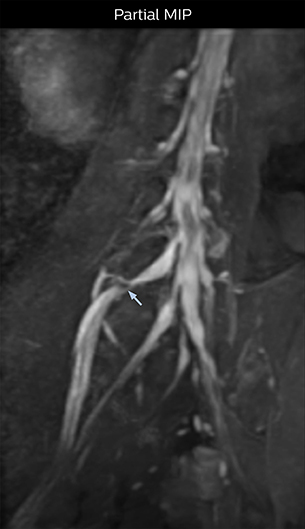

At Northern Fukushima Medical Center in Japan, excellent MRI visualization of nerves helps support confident diagnoses and informs surgical treatment decisions for patients with lower limb symptoms. MRI technologist Tanji and orthopedic surgeon Dr. Yabuki share how direct nerve visualization with the 3D NerveVIEW method adds information when diagnosing atypical herniations. The additional insights changed their way of working and benefit their patient care, as illustrated by some clinical examples.

“In patients with lower extremity neurological symptoms, NerveVIEW helps us to determine the disease matching the patient’s symptoms by directly visualizing the nerves. We use the sequence mainly, when there is suspicion of intraforaminal stenosis, extraforaminal stenosis or lateral disc herniation, which is often based on routine T2- and T1-weighted images. Additionally, the excellent depiction of the course of nerves makes NerveVIEW a good navigator when applying treatment such as block therapy or surgery.”

“In such case, we would then browse through axial T2-weighted MR images slice by slice and mentally reconstruct the actual situation based on both radiculography and MRI. Fortunately, NerveVIEW can now very well show nerve courses and presence of nerve compression or edema in one single image series.” “We have often seen NerveVIEW directly depict details of the nerve compression that were not observed by radiculography. Therefore, we think that with NerveVIEW we can reduce the number of invasive examinations, especially for some patients with lumbar plexus symptoms.”

“Before NerveVIEW, diagnosis by MRI alone was sometimes difficult, unless there was a strong suspicion based on clinical symptoms,” says Shoji Yabuki, MD, DMSc, Orthopedic surgeon at Fukushima Medical University School of Medicine. “This is why we routinely perform selective lumbosacral radiculography (nerve root block) and x-ray in such cases. However, radiculography can only depict nerves as far as the contrast agent reaches. When a nerve is distorted by compression, the contrast agent will not pass through this compressed area, preventing us from evaluating the full nerve compression.”

The key concept in MR neurography, Dr. Yabuki stresses, is the ability to directly visualize spinal nerves, versus inferring the presence of pathology indirectly. “Before NerveVIEW, we estimated compression of the nerve by looking for the presence or absence of fat signal on other MR images,” he says.

“For example, in sagittal images, when the presence of fat is observed in the intervertebral foramen, it suggests that there is a margin around the nerve. Similarly, the absence of fat indicates that the nerve is being compressed. So, we used to deduce nerve compression indirectly. With NerveVIEW, however, we can observe the condition of the nerves directly, regardless of the presence or absence of fat. We always prefer such direct observation of anatomy over having to make an inference about it.”

“Although symptoms of typical disc herniation and atypical hernia are very similar, the actual site of herniation is different. It is therefore important to characterize the nerve’s condition both inside and outside of the intervertebral foramina. “Conversely, if we see no abnormality in NerveVIEW, we can assume at least that there is no severe condition that requires surgery. Like this, it can help us avoid unnecessary surgery. NerveVIEW can have a tremendous impact in this way.”

“NerveVIEW is really useful for those cases where a nerve disorder is strongly suspected based on the clinical examination but our regular MRI images do not show any findings. These atypical herniations and spinal canal stenosis, occurring in 5% to 15% of the total lumbar herniation/stenosis cases are our main target when using NerveVIEW,” says Dr. Yabuki.

“The intra-luminal signal of veins, especially around the intervertebral space, can be suppressed well with NerveVIEW. As a result, we can easily observe the detailed nerve structure around the posterior ganglion,” he says. “This is why we use 3D NerveVIEW for intraforaminal stenosis and extraforaminal stenosis/herniation (lateral disc herniation). On the other hand, if herniation is suspected to exist inside the dorsal root ganglion (DRG), balanced TFE or ProSet-FFE is applied. NerveVIEW is not suitable for evaluating the median type of herniation.” The SE-EPI DWI-based method for MR neurography works well for large FOV exams like whole-body MRI, but focal examination of nerves is often limited by the attainable spatial resolution (both inplane and slice direction) and geometric distortion. “3D NerveVIEW achieves higher in-plane resolution – close to our other routine spine sequences – and the source images can be used instead of adding a fat-suppressed T2-weighted sequence,” Tanji says.